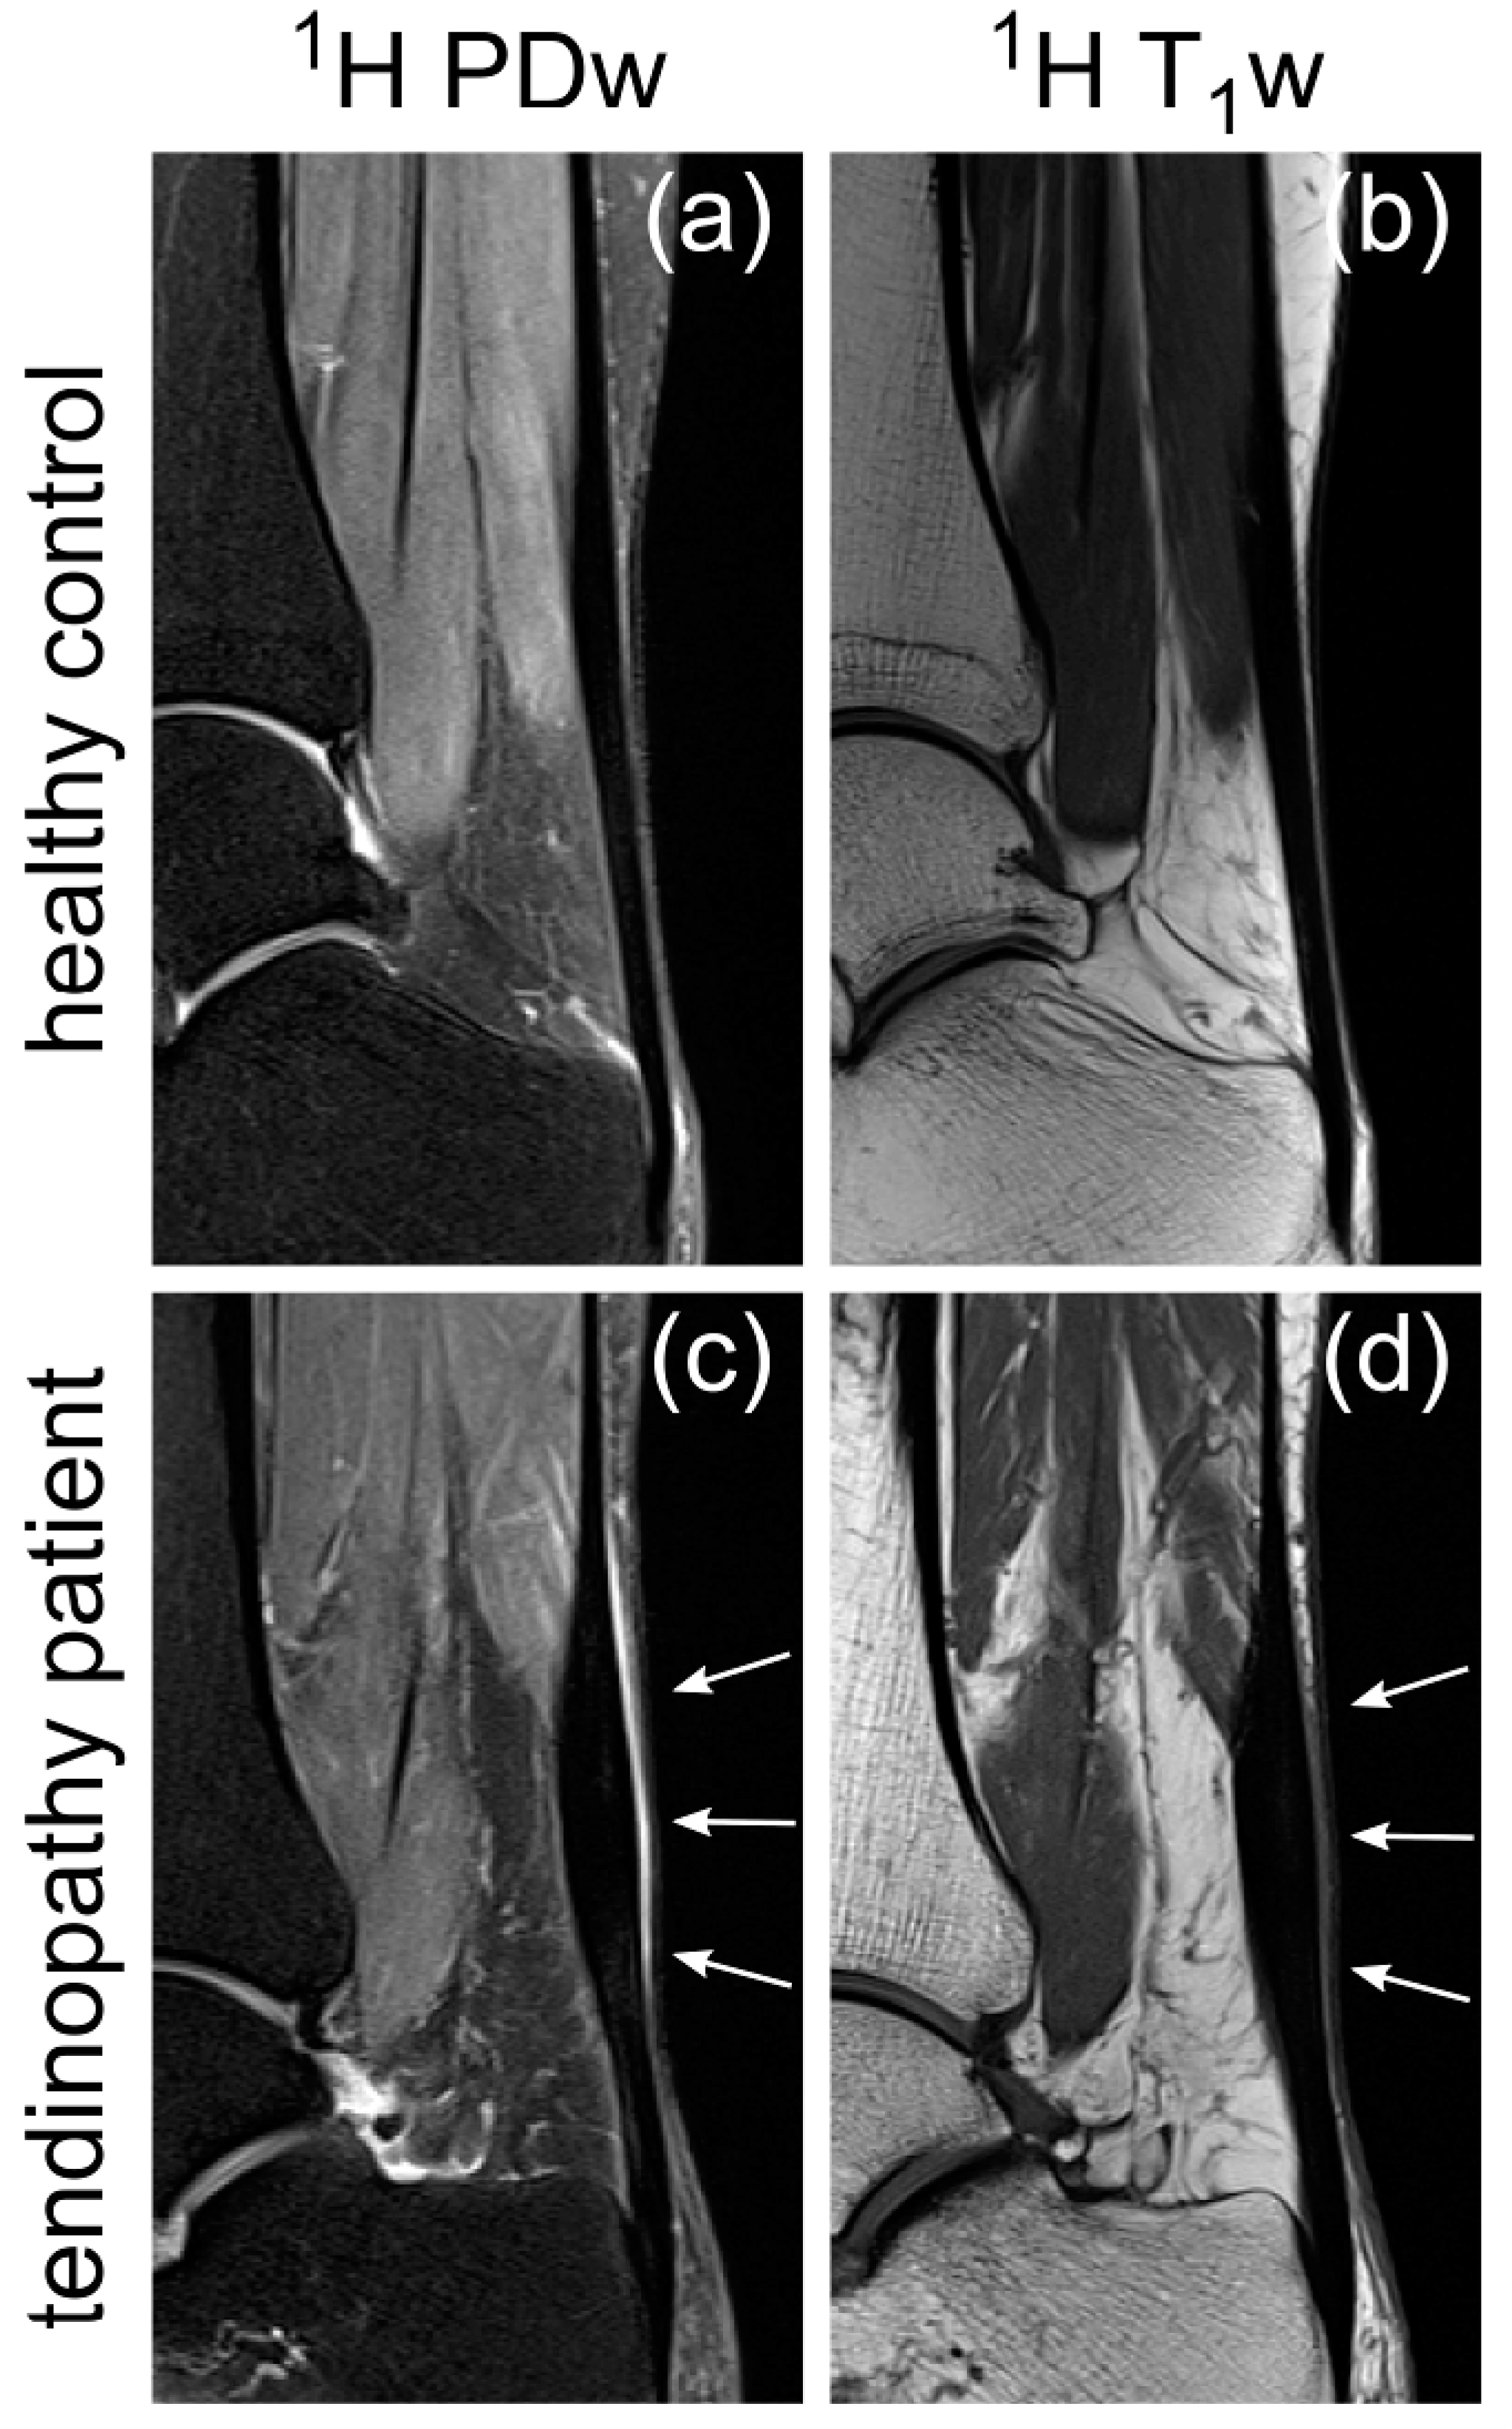

4.2. MRI